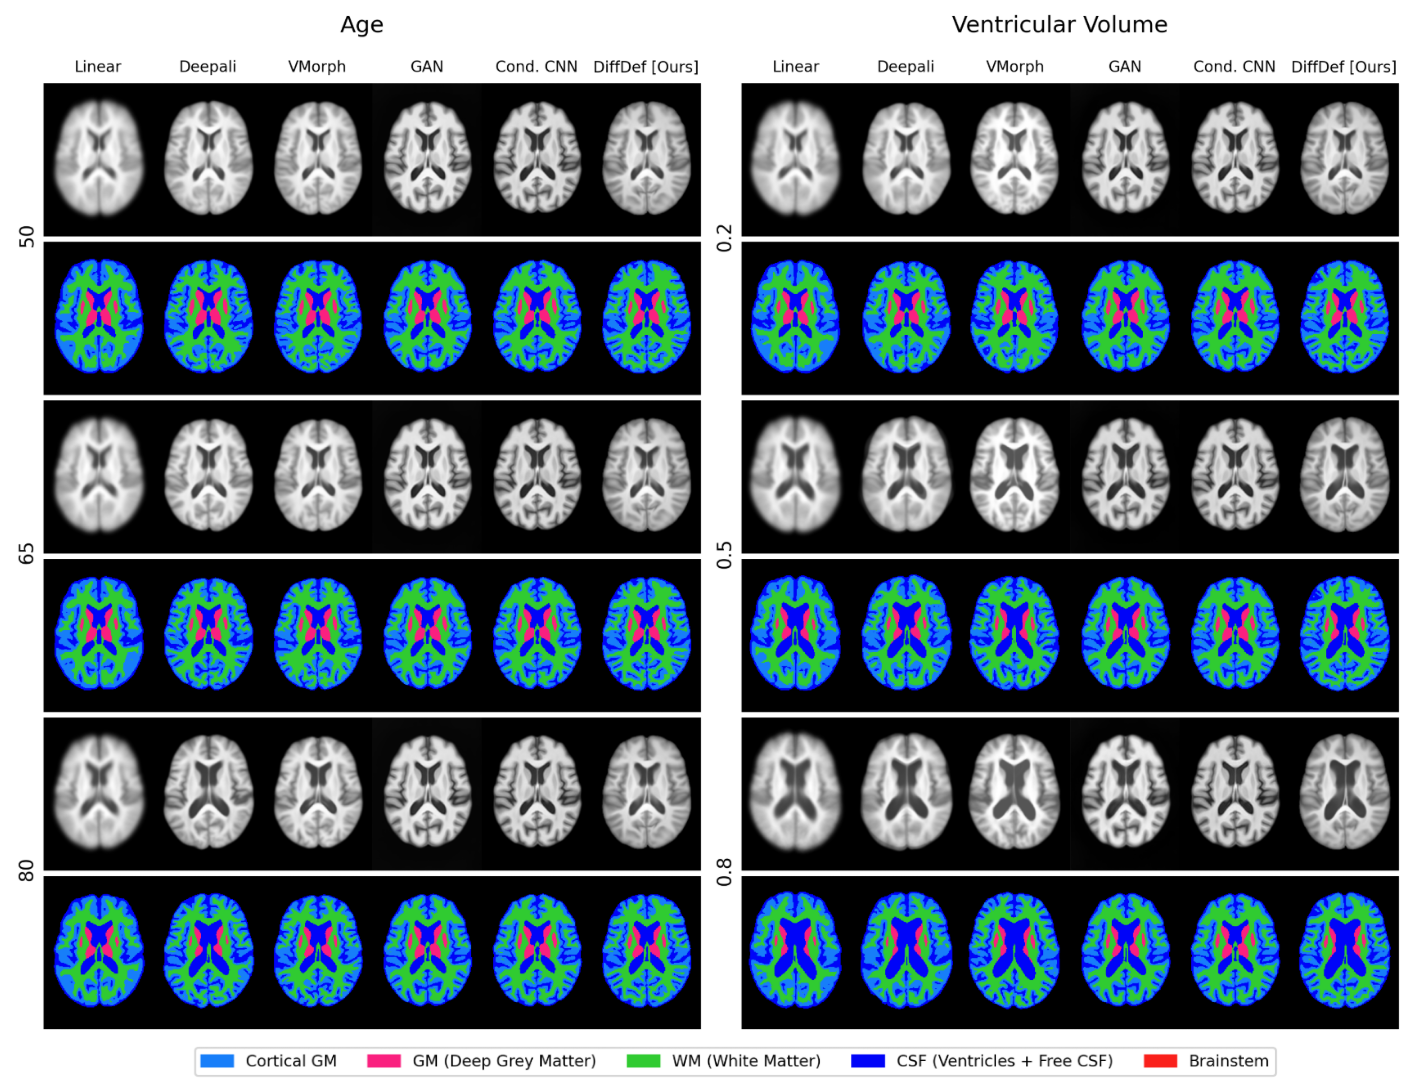

Refer to caption

Figure 3: Qualitative results of the proposed method (DiffDef) and baseline models, conditioned on normalized ventricular volumes (0.2,0.5,0.80.20.50.80.2,0.5,0.80.2 , 0.5 , 0.8) and ages (50,65,8050658050,65,8050 , 65 , 80 years). DiffDef, the only method that generates displacement fields, effectively captures the anatomical progression associated with both conditions, e.g. the growth of the ventricular volume in both cases. At the same time, it preserves the appearance characteristics of the original cohort, maintaining consistency with the underlying intensity distribution.

Figure 3 illustrates the resulting brain atlases of all the different methods conditioned on the ventricular volume and age. Comparing our method (last column) to the conventionally generated atlases (Linear, Deepali and VXM), we achieve sharper boundaries while maintaining the intensity distribution of the dataset and the accurate morphological features. Since our method deforms an existing population atlas with the generated deformation field, it does not introduce any intensity shift. Moreover, the deformation field is regularised during training, ensuring that no unrealistic or out-of-distribution anatomical structures are generated. In contrast, GAN and Cond. CNN are prone to generate unrealistic intensities and noisy backgrounds as acknowledged in [8]. They require masking as an additional post-processing step to mitigate this effect. Furthermore, brain shapes for both GAN and Cond. CNN vary noticeably from the expected brain shape that the conventional methods compute. Indeed, the frontal lobe is narrower both for the GAN and Cond. CNN-generated case, in all generated conditions.

An increase in ventricular volume due to the atrophy of the surrounding brain tissue is a well-studied biomarker in neurological ageing [54]. This is visible in all three conventional methods, GAN and our approach, while Cond. CNN fails to capture this effect consistently. Furthermore, our approach is the only one that generates a deformation field. This inherently enhances the interpretability of our method, allowing us to localise structural changes. We illustrate this in Figure 2, where the Jacobian determinants of the generated displacements are visualised alongside the final produced atlases conditioned on ventricular volume. The Eigenvalues of the Jacobian determinant indicate the magnitude of expansion (red) or compression (blue) in the image domain.